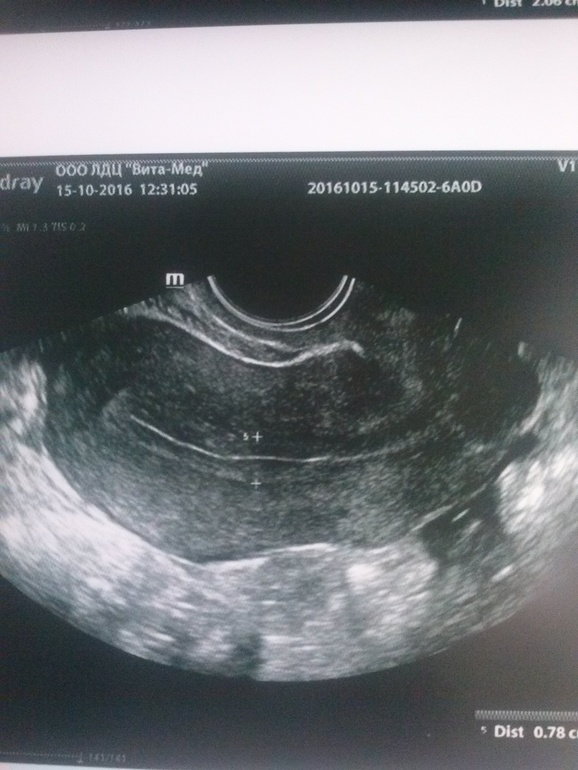

ого.. лапару делали... у меня подозрение на Хэ по узи, Г говорит типа единичные кальцинаты не страшно.. фото пришлю, может что скажете?

аа,вот белая полосочка означает кальцинаты... узист пишет подозрение на ХЭ ,а Гиня мол единичные кальцинаты.. но на физио отправила